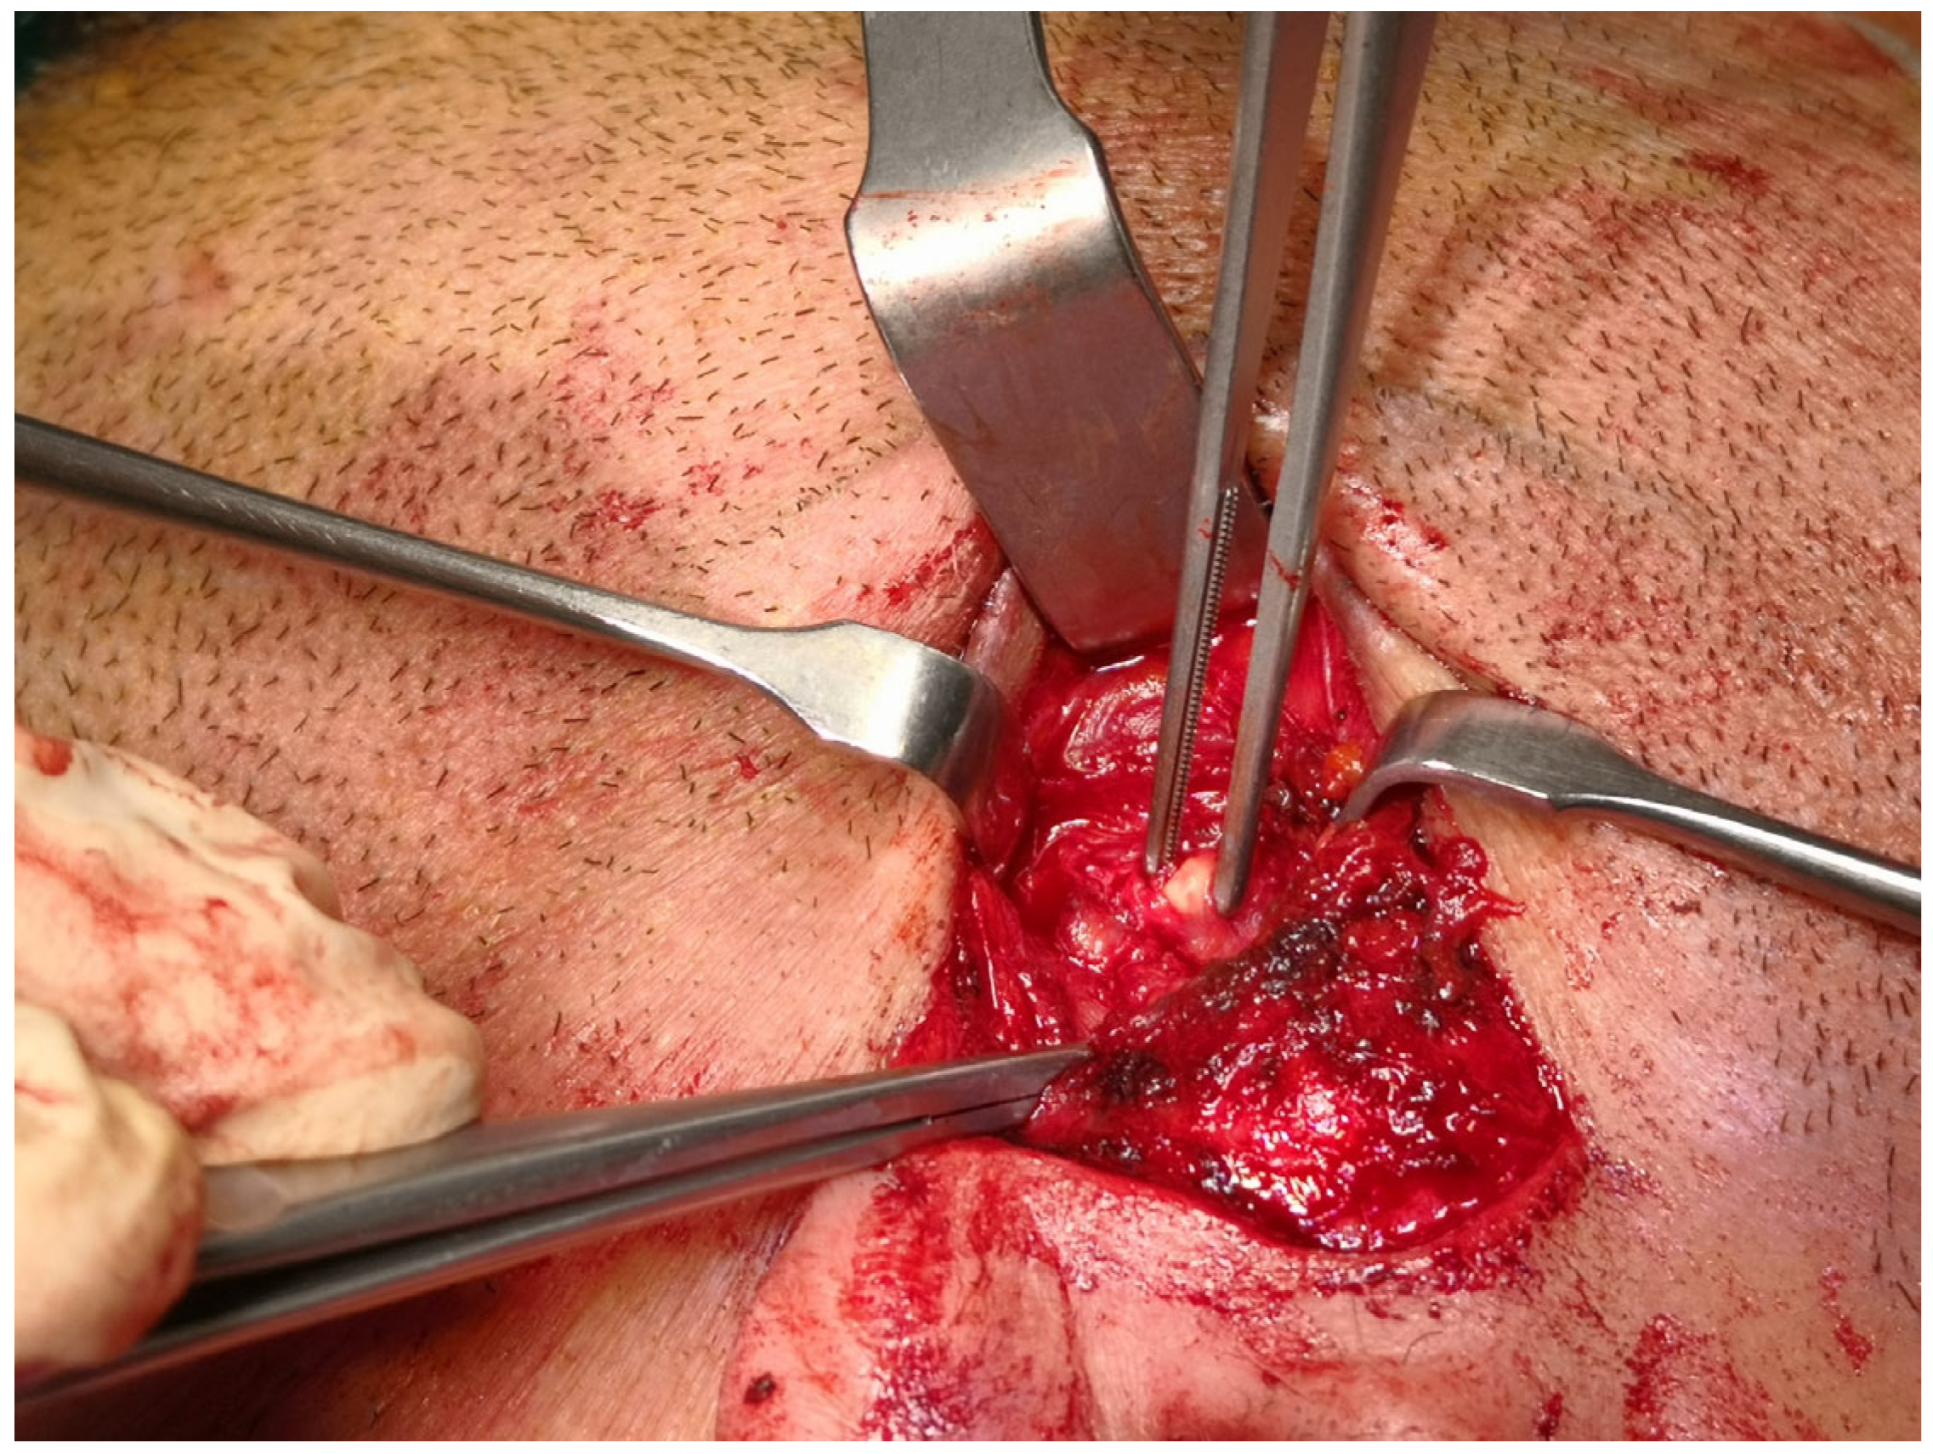

®, Bovie Medical Corporation, Clearwater, FL, USA) was used to check the functioning of the branches of the VII cranial nerve. The duct was then incised and opened under navigation guidance, and the stone was removed (

Figure 5) with dedicated dissectors; a further sialendoscopic exploration of the duct was made to exclude the presence of any residual stones, and a saline or antibiotic irrigation was made. The glandular acini were closed together and a hemostatic patch (Tabotamp

® Ethicon Sarl, Neuchatel, Switzerland) was placed over the incision; the parotid fascia and the skin incision were sutured. All patients maintained fasting for 48 h and a compressive dressing for at least 72 h; a peri-operative antibiotic prophylaxis was given (